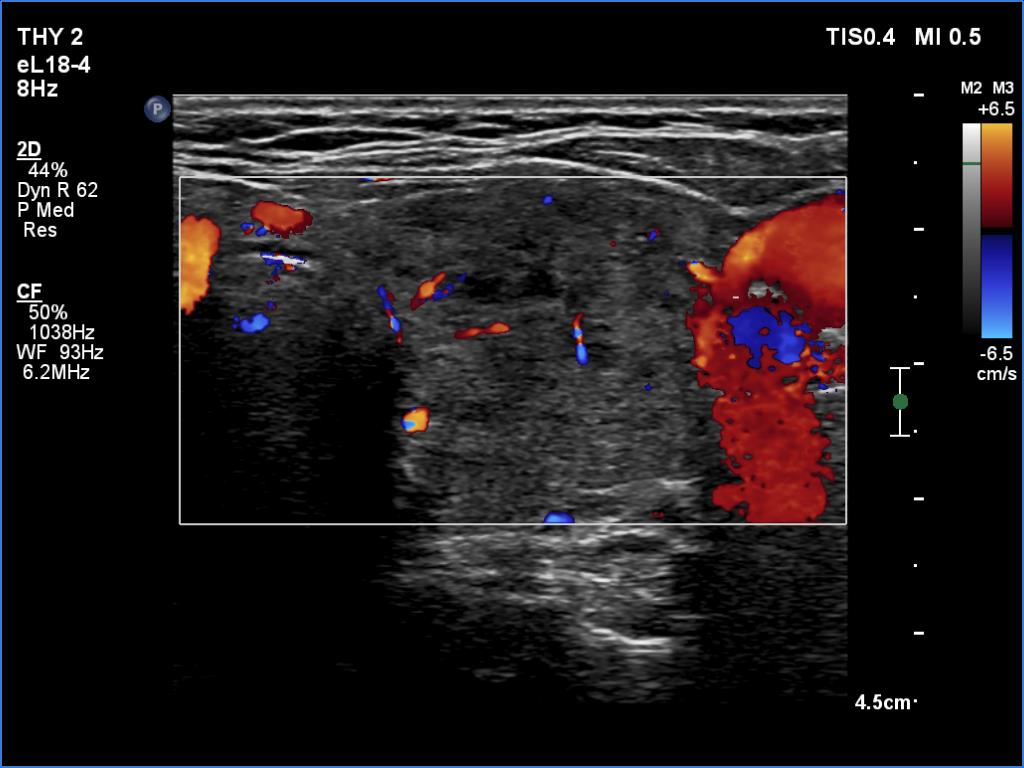

Graves' disease - case 2151

Three years after the first examination (ultrasonographic picture 8)

Right lobe, longitudinal scan

Left lobe, transverse scan, color Doppler mode. The vascular is decreased in this lobe.